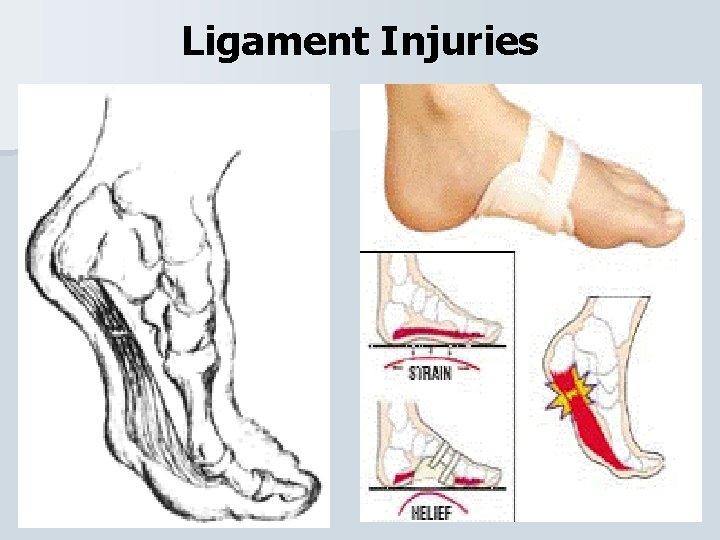

Ligament Injuries Arch Sprain An arch sprain can be caused by running on a hard surface, wearing improper footwear, or repetitive stress. • The athlete will report pain over the involved arch except the metatarsal arch will cause pain at the ball of the foot. • PRICES, strengthening and arch support. •

Ligament Injuries Lateral and Medial Ankle Sprain Majority of ankle sprains occur Inversion (85%) where Eversion (15%). • When the ankle inverts the lateral ligament are injured (ATF and calcaneofibular) and when it everts the medial ligamant (deltoid) is injured. •